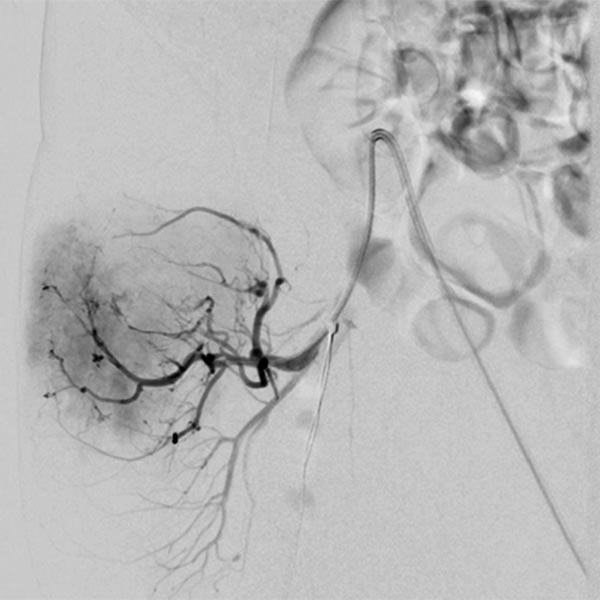

In view of massive coagulopathy prohibiting open surgery in this location and lack of improvement with drug therapy and replacement of platelets and coagulants alone, the decision was made to embolize the hypervascularized tumor. Digital subtraction angiography (DSA) shows the highly vascularized tumor supplied mainly from the right superior gluteal artery.

The tumor shows the typical tumor blush with diffuse, strong contrast enhancement on DSA after super-selective catheterization with the microcatheter.